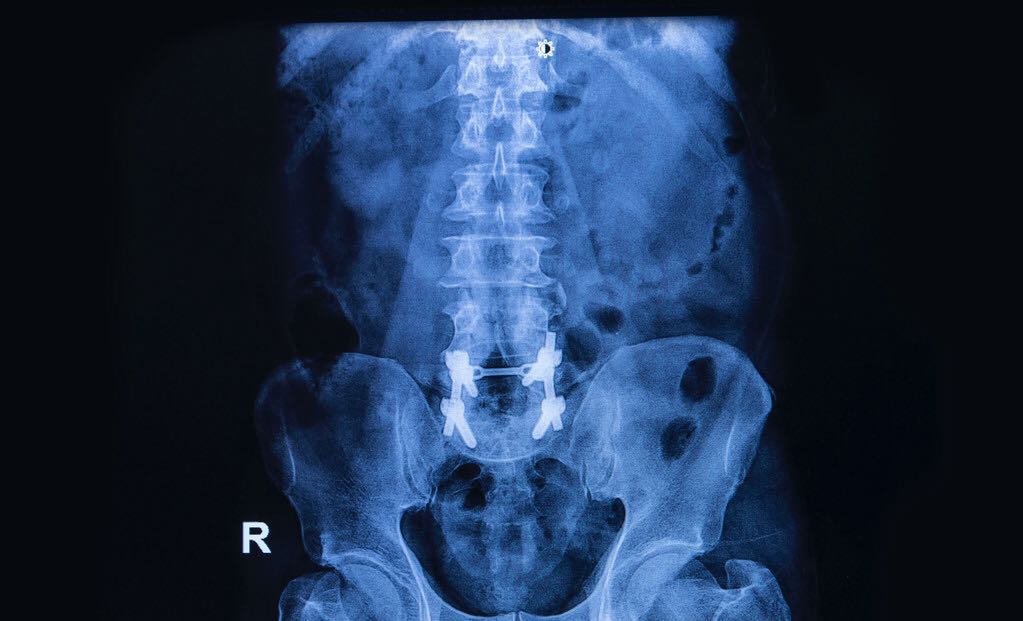

强直性脊柱炎有哪些症状呢?如何判断是否患有强直性脊柱炎?一般来说主要有这几个方面的症状:

①腰背疼痛。很多患者在最开始的时候,会出现臀部、髋关节、腰部、背部疼痛的情况,并且疼痛不断扩散。刚开始是分散的,间歇性的疼痛,慢慢发展到后面会变成持续性的痛,而且疼痛程度也是呈递增趋势。

②腰背僵直。在早上保持一个动作太久了要改变的时候就会不那么正常,就比如说,早上久坐久立之后,突然站起来或者突然坐下去,会感觉到腰部背部非常的僵硬,需要费很大力才能恢复过来。晚上睡觉的时候有时也会出现这种问题,就导致了翻身困难。

③引起关节炎。强直性脊柱炎会连累到身体其他很多的部位和关节。④有些人会出现疲劳、发热、消瘦等现象,视力也会受损。此外还可能会有压迫性神经炎、坐骨骨折脱位或者坐骨神经痛等病症。

强直性脊柱炎算是比较严重的一种疾病,因为它危害比较大,又没有彻底的治疗方法。很多人会因为患上这种病导致残疾。因为脊椎是人体非常重要的身体部位,上面又包含着非常多的神经,所以如果治疗不好非常容易导致残废。

脊柱强直,就是脊柱非常僵直,做正常的弯腰、翻身等一些动作会非常困难。要治疗强直性脊柱炎可以采用药物治疗,也可以是非药物治疗。